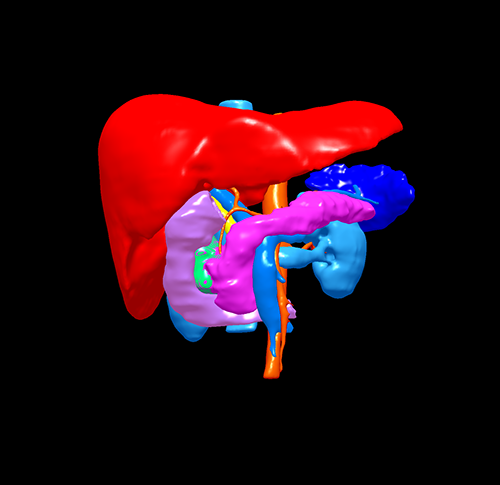

慢性胰腺炎伴假性囊肿形成